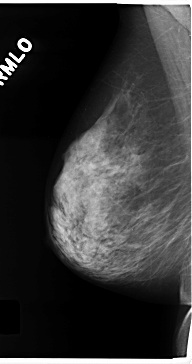

C_0175_1.RIGHT_MLO

RIGHT_MLO LINES 4720 PIXELS_PER_LINE 2496 BITS_PER_PIXEL 12 RESOLUTION 50 NON_OVERLAY